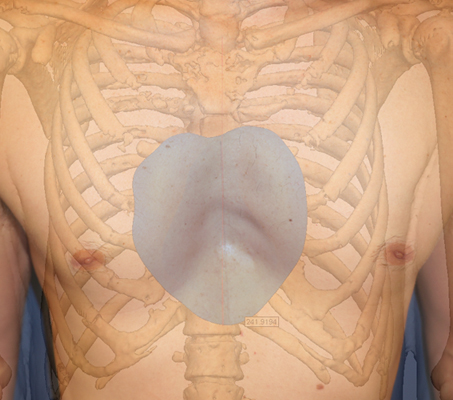

La tecnica di impianto su misura è una tecnica chirurgica minore che consiste nel riempire la concavità creata dal Pectus con un impianto personalizzato. Si tratta di un intervento rapido, a basso rischio, con un risultato immediato e una breve convalescenza.

In questa pagina, troverà i risultati di questa operazione a seconda del tipo di Pectus : mediale, asimmetrico, più o meno profondo o lungo.

Tipo 1 : Mediano, profondo e simmetrico,